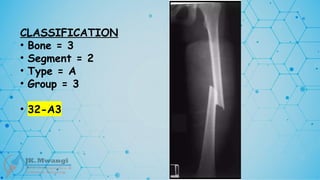

CLASSIFICATION

• Bone = 3

• Segment = 2

• Type = A

• Group = 3

• 32-A3